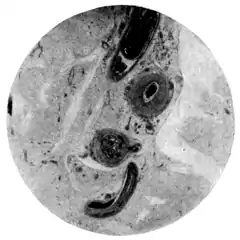

|style="padding-right:1em;"|Fig. 1.—Schistosomum japonicim in vessels of mesentery.

(Microphotograph: Dr. Henderson.) ||Fig. 2.—Eggs of Schistosomum japonicim embedded in walls

of appendix vermiformia.

(Microphotograph: Dr. Kerr.)

|colspan=2|Plate XIV.